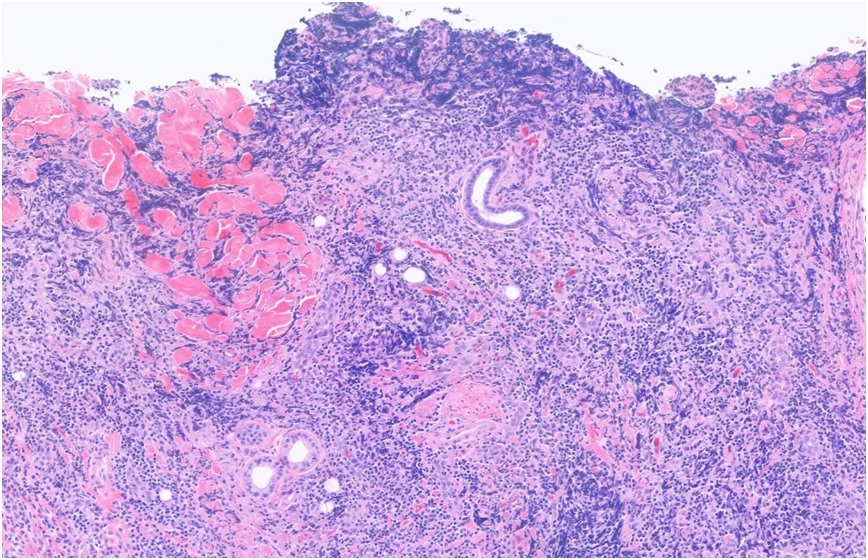

45 Year old male with forehead biopsy Itchy, raised plaque on on frontal hairline (no rash elsewhere). Red patches ?Seborrhoeic dermatitis (raised, erythematous)